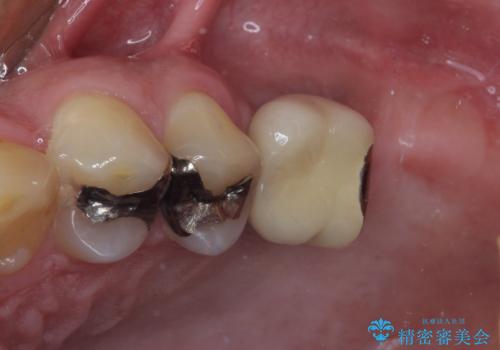

- 黄ばんだ前歯や目立つ奥歯の銀歯をきれいにしたいとのことで来院された患者様です。

欠損している歯や、割れてしまって抜歯の必要な歯などがあり、咬合力が強いため欠損部はインプラント補綴を前提に治療を行うこととしました。

小さい修復物の銀歯が装着されている歯はセラミックインレーにて、その他はオールセラミッククラウンにて補綴治療を進めることとしました。